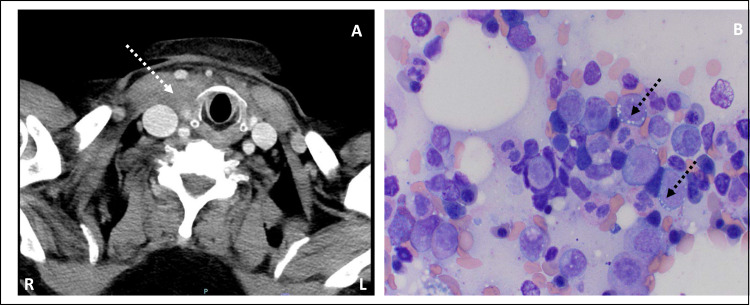

VEXAS syndrome (vacuoles, E1 enzyme, X-linked, autoinflammatory, somatic) is a recently described adult autoinflammatory disease associated with somatic mutations in the gene encoding ubiquitin-activating enzyme 1 (UBA1) in hematopoietic progenitor cells. Loss of function mutation of UBA1 results in a broad range of inflammatory and hematological conditions. To date, there are no established targeted therapies for VEXAS syndrome, especially in patients who are refractory to conventional immunosuppressive treatments. We report the case of a 75-year-old Hispanic gentleman with hypertension, dyslipidemia, and type 2 diabetes mellitus who presented with a 2-year history of intermittent fever, weight loss, recurrent sore throat, recurrent soft tissue swelling (mimicking cellulitis), oligoarthritis, erythema nodosum, and venous thrombosis. Laboratory workup showed elevated inflammatory markers, macrocytic anemia, and leukopenia. Patient received several rounds of antibiotics and corticosteroids for presumed cellulitis and throat infections, with limited improvement. He subsequently underwent bone marrow biopsy, which showed characteristic vacuolization of myeloid precursors. Genetic testing revealed a missense mutation in UBA1, Exon 3 c.121A>G, pMet41Val. He was diagnosed with VEXAS syndrome. He was started on corticosteroids and Tocilizumab (anti-IL-6 receptor antibody). He had severe leukopenia with Tocilizumab and was switched to Ruxolitinib (Jak inhibitor). He had a significant clinical response to Ruxolitinib and was able to be tapered off prednisone. Our case report and review of the literature report Jak inhibition as a possible target for the management of inflammatory symptoms of VEXAS.